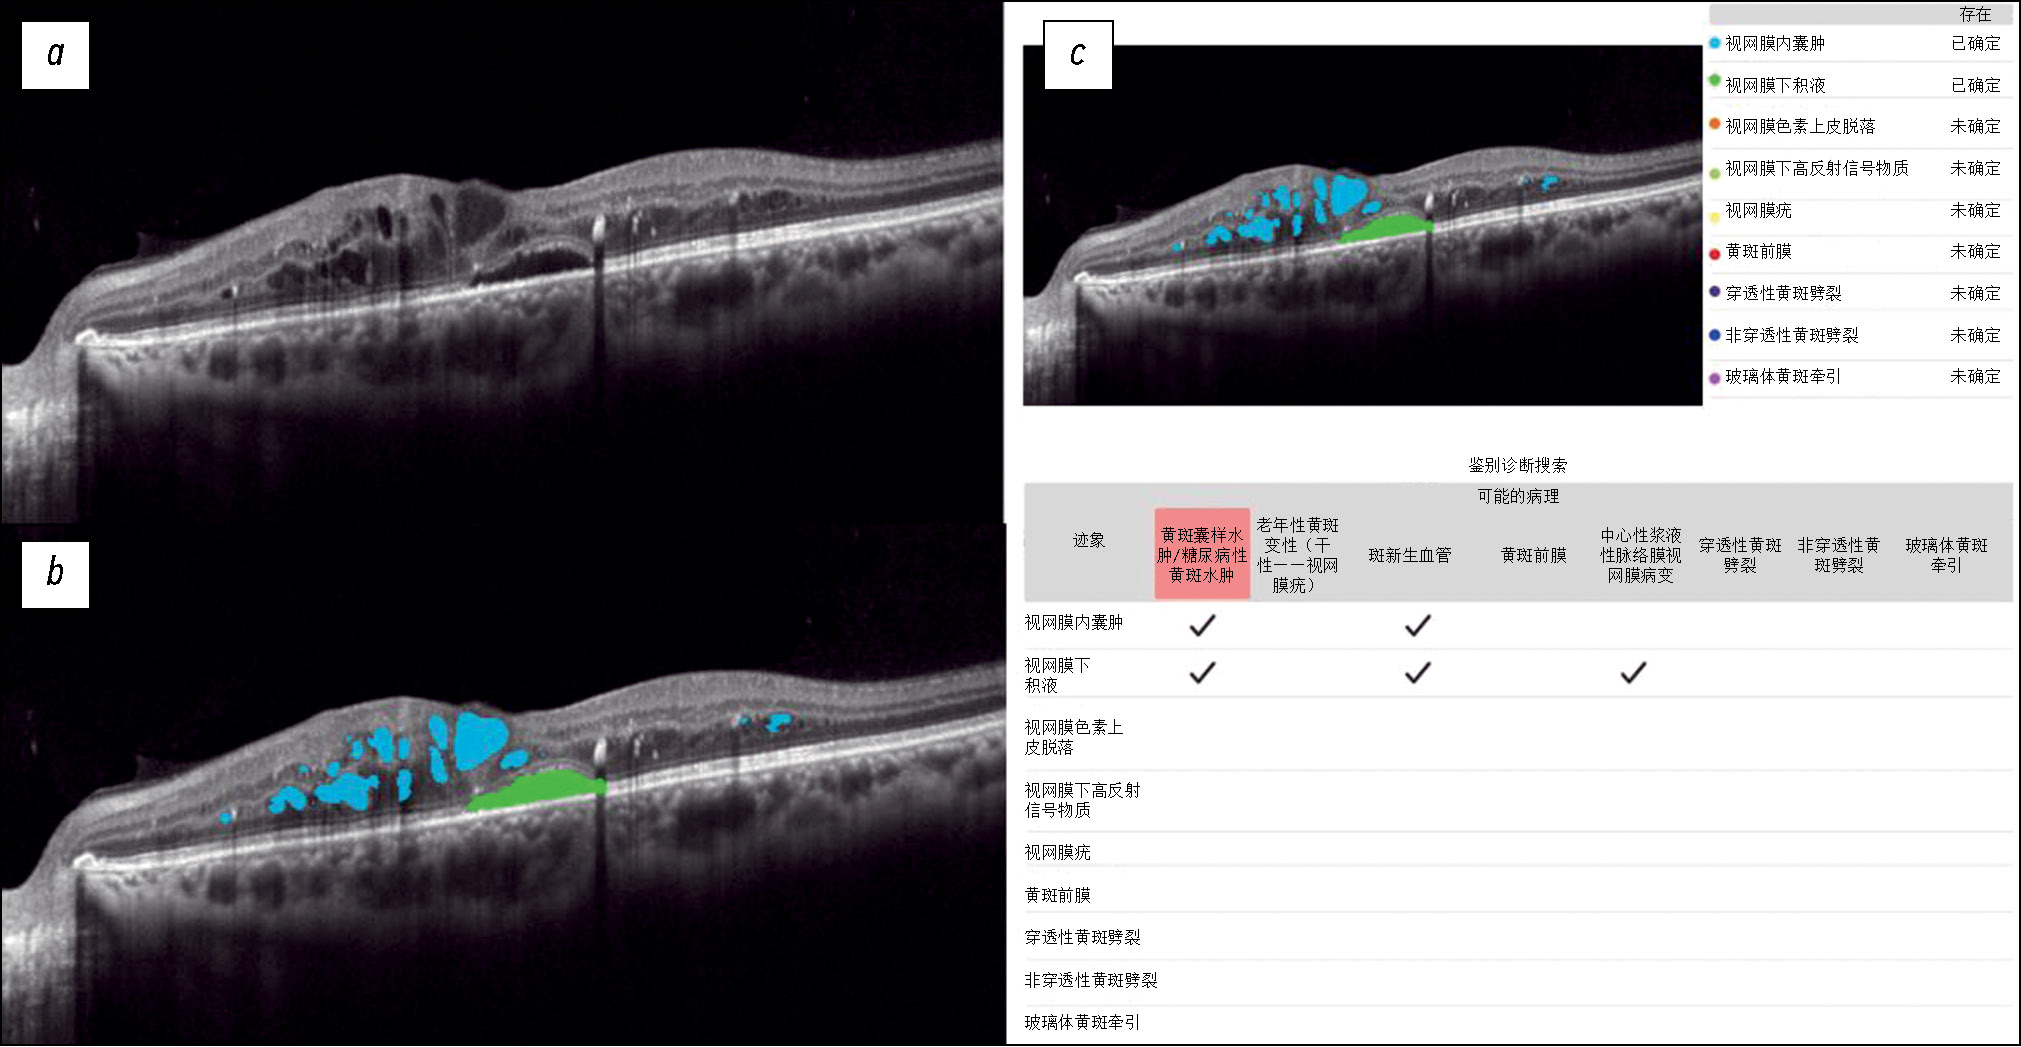

Fig. 1 shows a structural OCT scan of the macular zone of patient B (54 years old) with type 2 diabetes mellitus. The ophthalmologist’s report recorded DME. In the analysis of the structural OCT scan by Retina.AI, the algorithms segmented the following pathological signs: intraretinal cysts, subretinal fluid. In conclusion, the patient was diagnosed with DME.

Fig. 1. An example of the optical coherence tomography scan analysis of a patient with diabetic macular edema by the artificial intelligence algorithm: a — structural optical coherence tomography scan; b — optical coherence tomography scan after segmentation of the pathological features (subretinal fluid — green mask, intraretinal cysts — blue masks); c — scan analysis report (the reporting table of the differential diagnostic search, probable pathology is highlighted in red — macular edema).